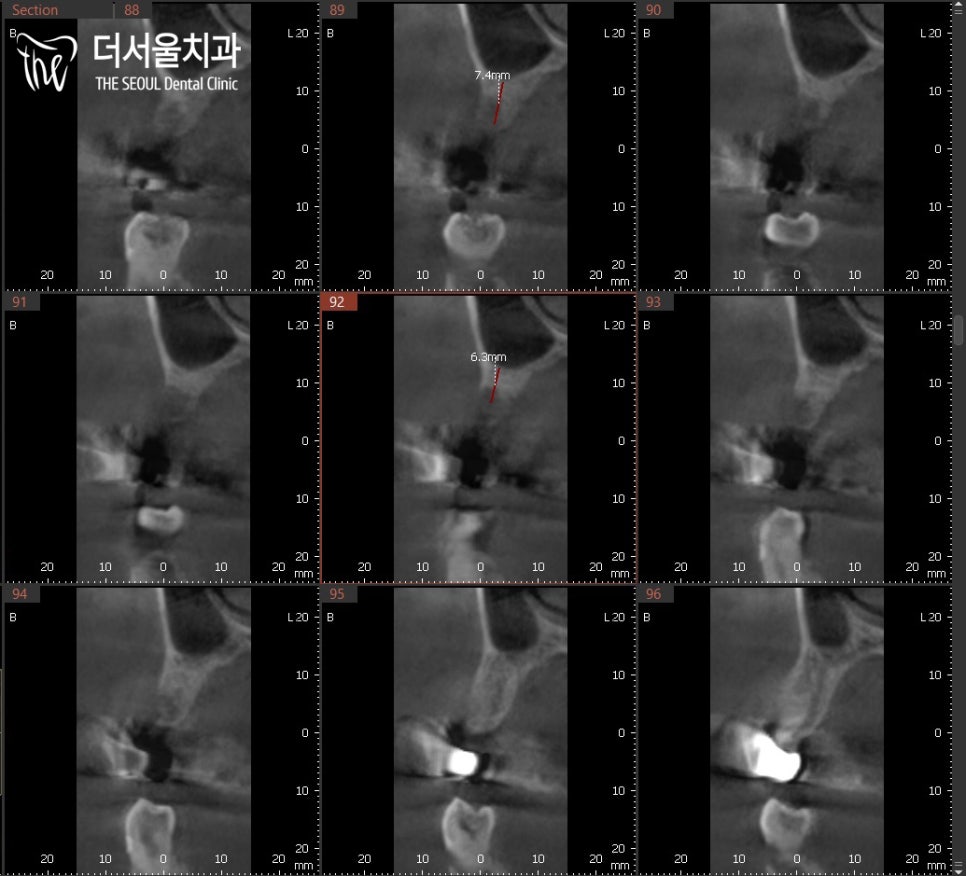

2. 정밀 검사

이런.. CT로 확인해봤더니

정말 뼈가 많이 녹아있었네요.

이정도라면 불가능하다는 소리가 나올만 합니다.

그러나 태평동 치과는

할 수 없는 것을 할 수 있게 만들죠.

뼈이식을 통해 뼈를 두껍게 만들어주면 됩니다.

물론 상악동과 가깝기 때문에

거상술로 막을 들어올린 뒤,

생성된 공간 속에 뼈재료를 넣어줍니다.